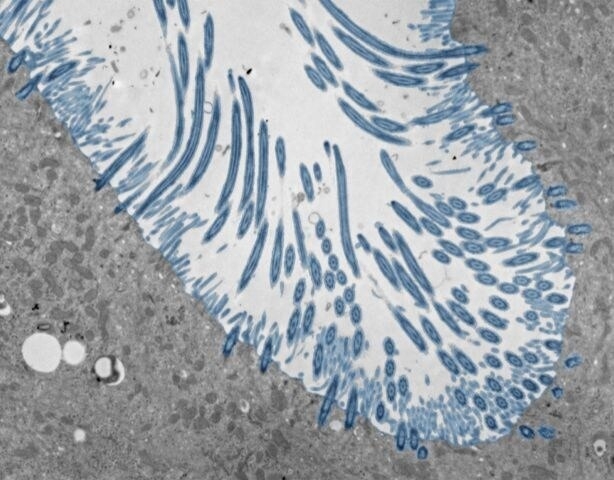

Pour comprendre cette variabilité, des scientifiques ont recréé un "nez en boîte". Ils ont cultivé des cellules souches nasales pour former des organoïdes, des versions miniatures de l'interface entre notre nez et l'air. Ces modèles complexes, dotés de cils vibratiles et de cellules productrices de mucus, ont ensuite été infectés par un rhinovirus. L'observation de milliers de cellules a permis de décortiquer la chorégraphie de la réponse immunitaire.

cellules nasales

Un organoïde nasal est une version miniature et fonctionnelle de la paroi interne du nez, cultivée en laboratoire à partir de cellules souches. Il permet aux scientifiques d'étudier comment les virus, comme le rhinovirus, interagissent avec les cellules humaines dans un environnement contrôlé, ce qui est impossible à faire sur des animaux qui ne sont pas sensibles à ce virus.